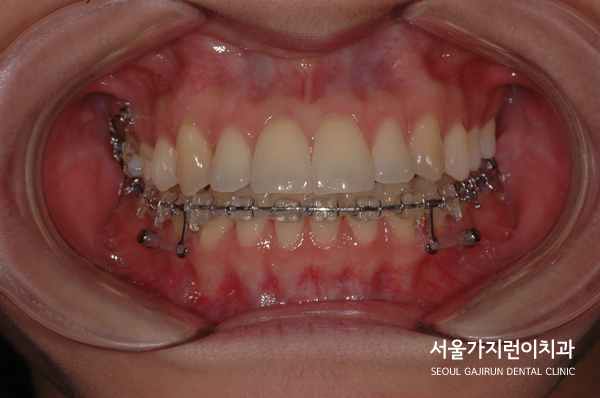

환자 분의 경우 미니스크류를 이용해 상악 우측 어금니를 후방으로 이동시키는 과정을 밟았는데요. 좌측 어금니와의 대칭을 맞추기 위해 진행한 상황입니다. 또 하악의 가지런한 치아배열을 만들기 위해 미니스크류를 적극적으로 활용했는데요. 미니스크류는 치아이동에 필요한 강한 힘을 균등하게 줄 수 있기 때문에 위, 아래 식립한 것을 상기 사진으로 확인해볼 수 있습니다.

짜잔! 환자 분의 경우 1년 만에 치아배열이 좋아진 것을 확인해볼 수 있었는데요. 중심선도 개선이 되었고 앞니의 뻐드러짐 정도로 눈에 띄게 나아진 것을 확인해볼 수 있었습니다. 비발치로 진행했는데도 치열이 가지런하게 정돈이 되었죠. 어금니의 위치도 좋아졌고 중심선도 맞고 치열까지 맞춰 성공적인 교정치료가 되었습니다. 비발치로도 얼마든지 무리하지 않고 치료플랜을 수립해볼 수 있는 것이죠.